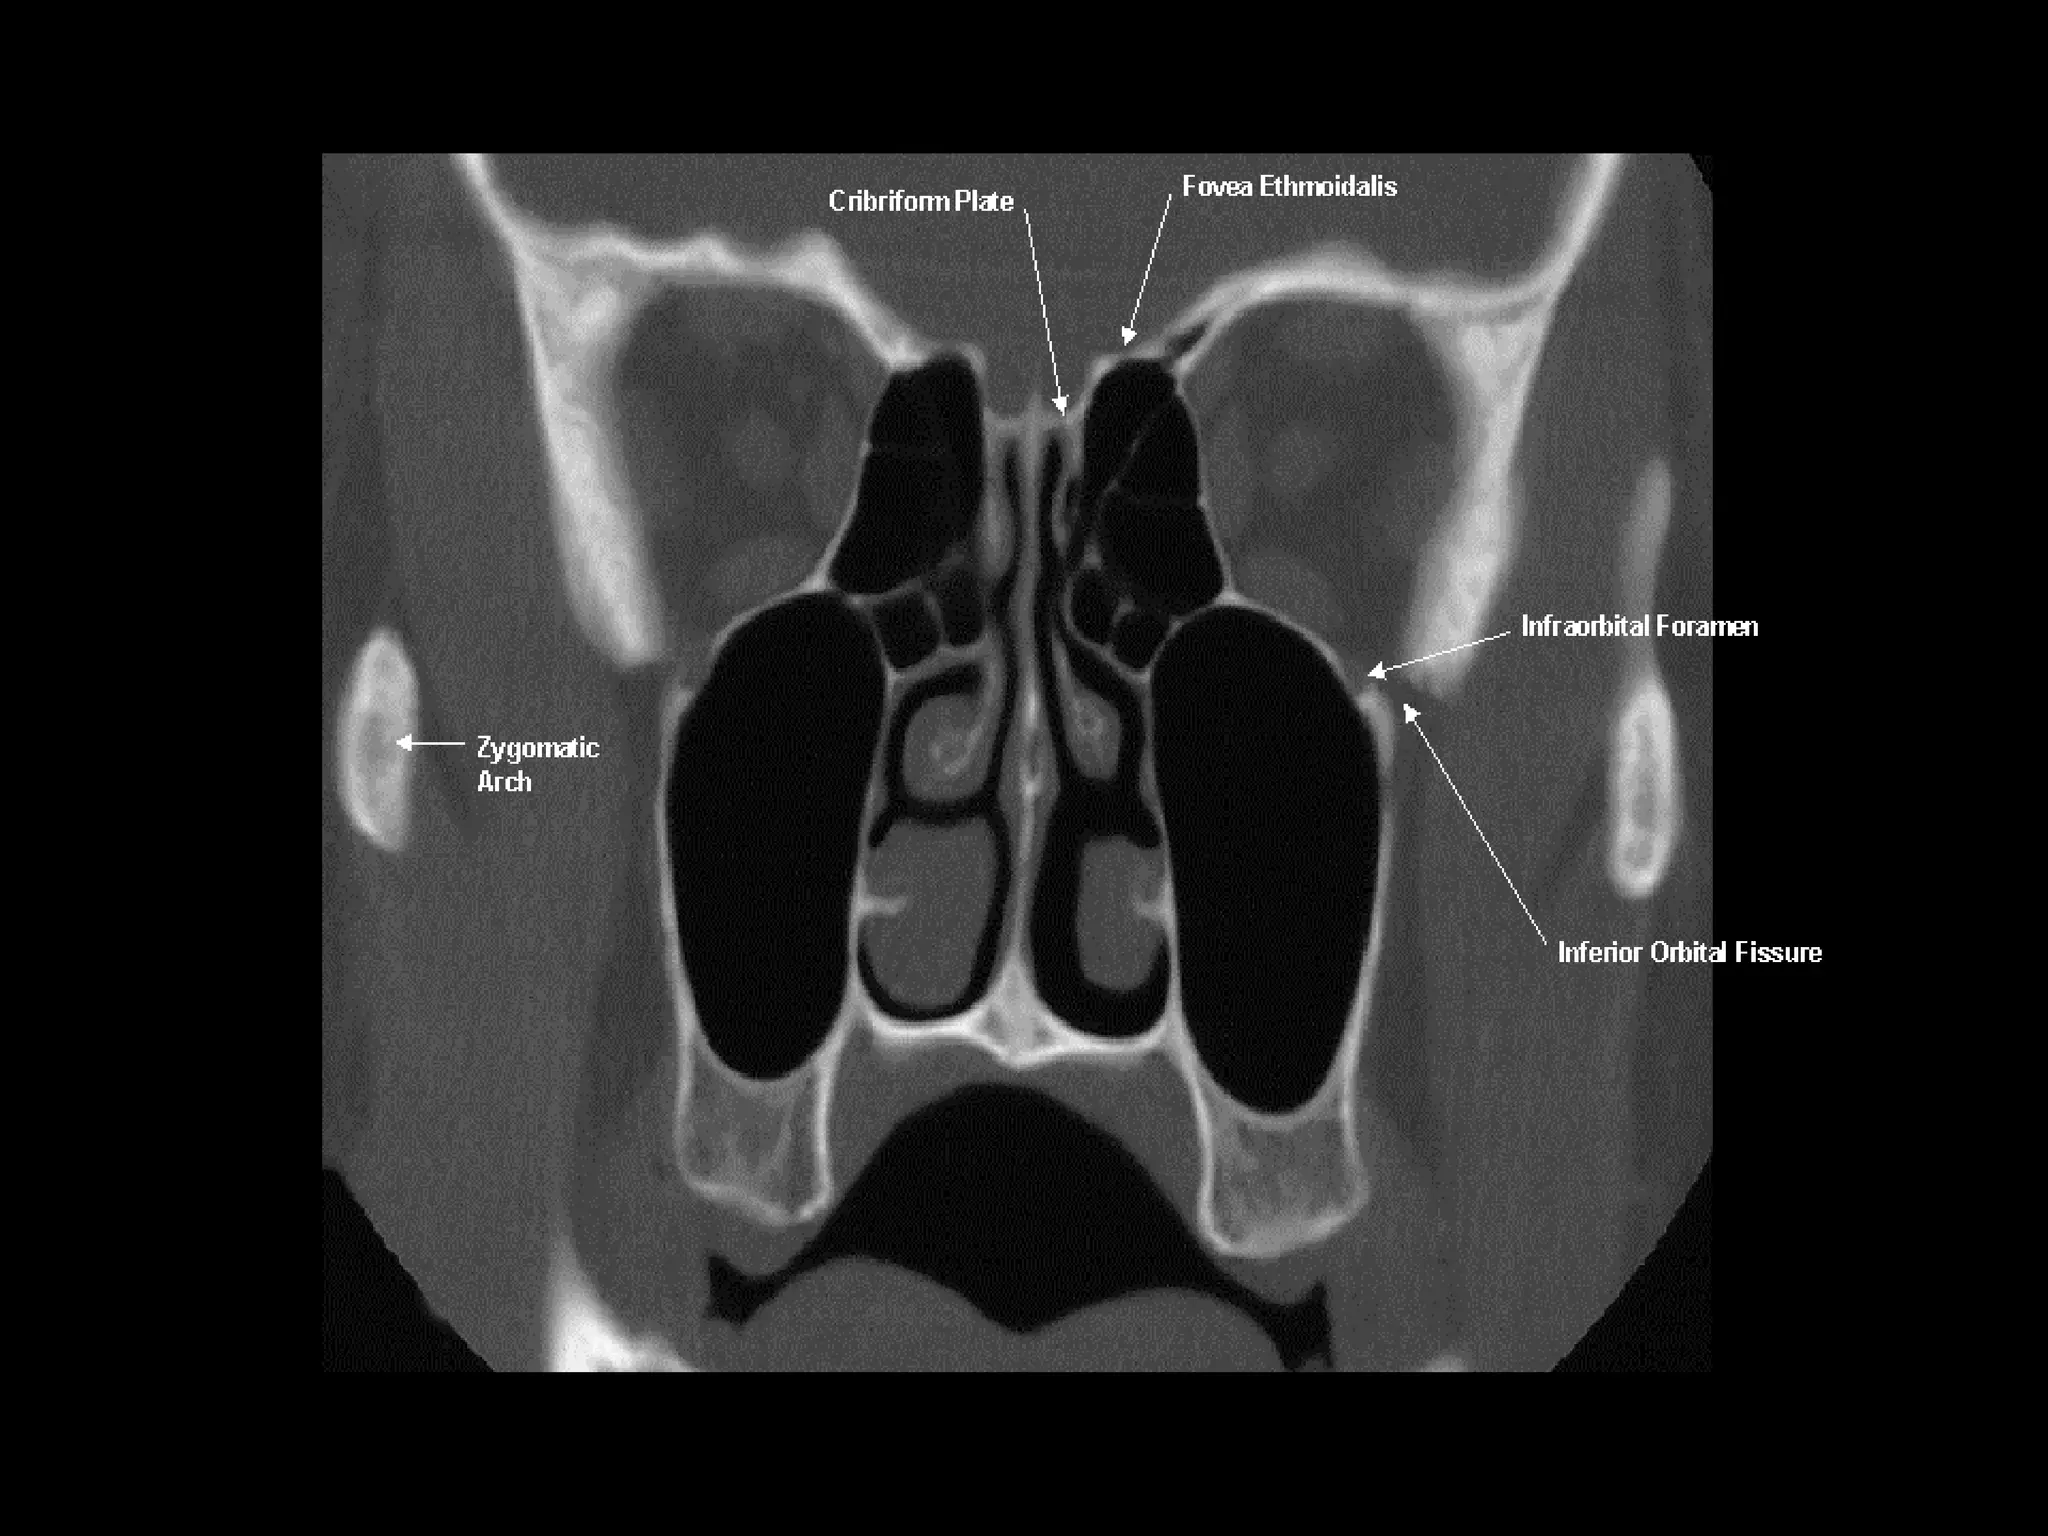

Radiographers are medical professionals who perform diagnostic imaging examinations and procedures to help physicians diagnose and treat diseases. They work under the supervision of radiologists to operate X-ray, CT, MRI, ultrasound and other medical imaging equipment and must have a strong understanding of human anatomy and pathology. Radiographers are responsible for correctly positioning patients, ensuring proper imaging techniques are used, and evaluating the quality of the resulting images.